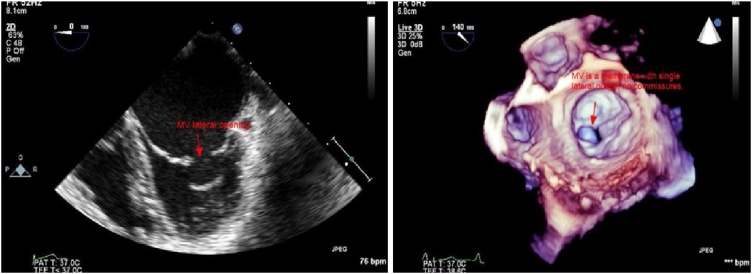

Fig. 4.

Left: TEE 2D mid esophageal view, apparent MV with two leaflets. Right: 3D surgical view of the mitral valve, a single oval orifice at the lateral part of the membrane like uni-leaflet mitral valve, there is no commissures seen.

Transthoracic echocardiography (TTE): The parasternal long-axis view showed that the MV appeared to have two leaflets (Fig. 3 left and Video 1), parasternal short-axis view showed the single orifice at the lateral one third of the MV, the medial two thirds were fused (Fig. 3 right and Video 2). Apical 4-chamber view showed flow acceleration through the stenotic lateral orifice of the MV (Video 4). Transesophageal echocardiography (TEE): In mid esophageal 4-chamber view there was what looked like two MV leaflets attached to a thickened chordae, (Fig. 4 left and Video 4) in 2-chamber views, the subvalvular apparatus looked to be amalgamated forming a mass below the posteromedial part of the MV (Fig. 5 left and Video 5). With color, there was an acceleration of flow through a lateral orifice of the MV (Video 5). In transgastric long-axis view of LV, there were two papillary muscles, the posteromedial one which was larger with fused chordae looked like the papillary muscle was directly inserted in the leaflet with the absence of intracordal spaces, the papillary muscle was inserted at the inferolateral wall of the LV near the apex. The anterolateral one was smaller with clearer chordal apparatus and was inserted at the med anterolateral wall of LV. In transgastric short-axis view, there was a clear appearance of both papillary muscles, excluding any possibility of parachute MV (Fig. 5 right and Video 6). Continuous Doppler flow revealed a mean PG of 19 mmHg across the MV indicating severe MS. In 3D images from the left atrial view, the MV appeared like a membrane with a single orifice in its lateral part toward the left atrial appendage, the area of this orifice by 3D was 0.52 cm2, and there were no commissures or even any residual lines at the site where the commissures should present (Fig. 4 right and Video 7). In 3D images from the LV view, the single slit-like orifice is clear with bulky amalgamated subvalvular apparatus (Video 8). The diagnosis of congenital severe mitral stenosis due to acommissural MV was confirmed, the case was discussed in our heart team meeting, and it was decided to go for MV replacement with a bioprosthetic valve. During surgery, the surgical appearance of the MVs confirmed our diagnosis by 3D (Fig. 6).